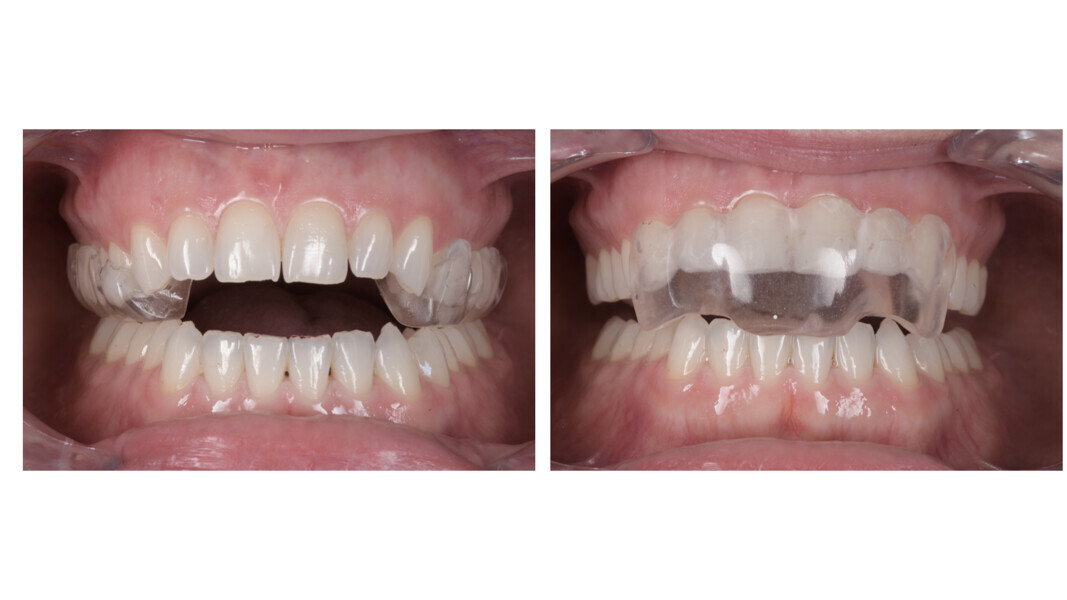

We selected a two-piece FACE splint, worn 24 hours a day in the posterior segment during the day and the anterior segment at night (Fig. 23). The splint therapy lasted for four months, during which a stable condylar position was achieved, the patient transitioned to a single arc of closure and full remission of TMD symptoms was obtained. As a result of mandibular posterior rotation, the occlusion changed, presenting with an increased anterior open bite (Fig. 24), an increased overjet (Fig. 25) and an increased Class II dental relationship (Fig. 26).

Given these findings, treatment was initiated with a two-piece FACE splint, designed to reposition the condyles and establish a stable occlusal relationship. The splint was worn for five months, during which time a stable condylar position, a single arc of closure and complete remission of TMD symptoms were achieved (Fig. 41). As demonstrated in the initial virtual articulator mounting, splint therapy produced a notable increase in the anterior open bite (Fig. 42).